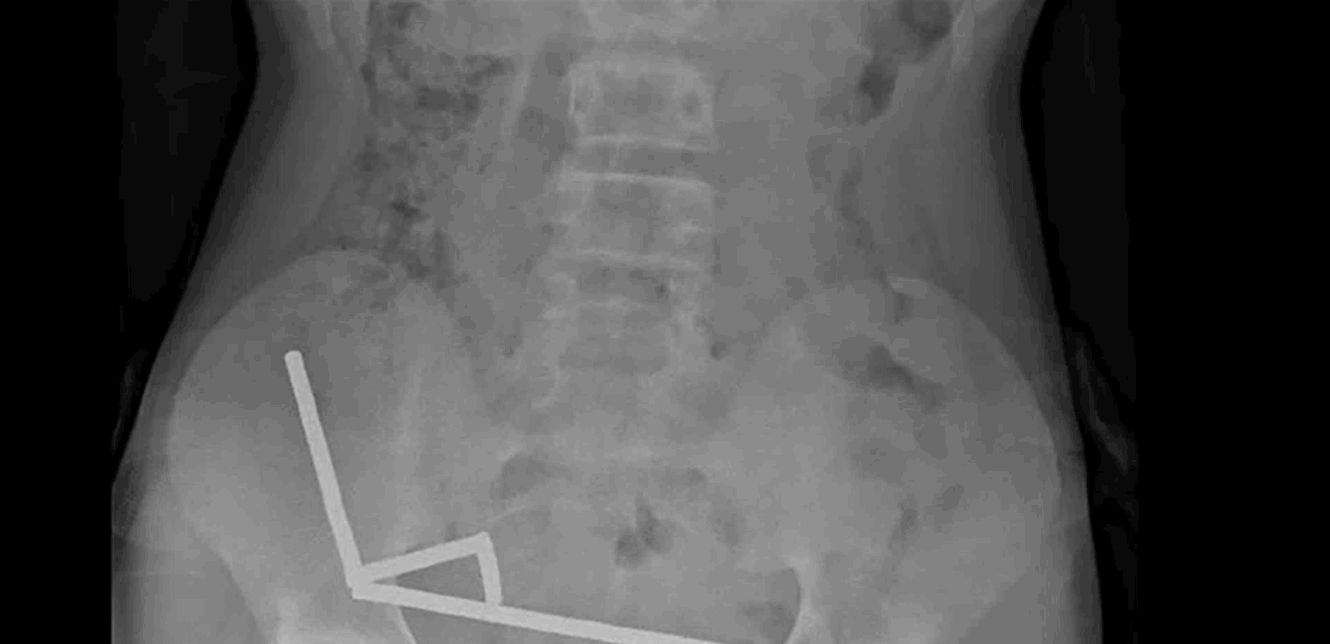

وقال التقرير أن الطفل "أكد أنه ابتلع ما يقرب من 80-100 مغناطيس عالي الطاقة (نيوديميوم) بأبعاد 5x2 مم قبل حوالي أسبوع". وأضافوا أن المغناطيسات، التي حُظرت في نيوزيلندا منذ يناير 2013، تم شراؤها من منصة التسوق الإلكترونية تيمو. وأظهرت الأشعة السينية أن المغناطيسات قد تكتلت معًا في أربعة خطوط مستقيمة داخل أمعاء الطفل.

وشرح التقرير: "يبدو أن هذه المغناطيسات كانت في أجزاء منفصلة من الأمعاء ملتصقة ببعضها البعض بسبب القوى المغناطيسية". كما أفاد الأطباء بأن ضغط المغناطيس تسبب في نخر (موت الأنسجة) في أربع مناطق من الأمعاء الدقيقة والأعور (جزء من الأمعاء الغليظة) للصبي.